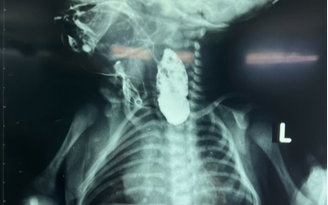

Hình ảnh X-quang trên bệnh nhi cho thấy đoạn thực quản gián đoạn rất dài

Lúc 40 tuần tuổi, bệnh nhi chào đời tại Bệnh viện Từ Dũ, các bác sĩ phát hiện ở bệnh nhi có những hiện tượng như sùi bọt cua ở miệng do gián đoạn thực quản không lưu thông được nước bọt, hô hấp khó khăn, đặt thông dạ dày thám sát bị vướng, X-quang gợi ý nghi ngờ teo thực quản. Bệnh nhi được chuyển đến Bệnh viện Nhi đồng 2 điều trị.